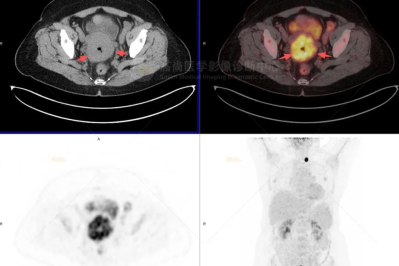

18F-FDG PET/CT 显像在乳腺外 Paget 病诊疗中的关键作用